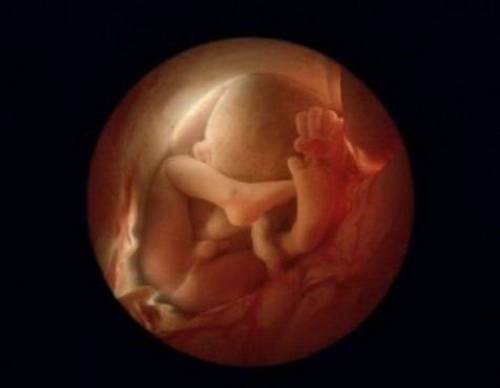

Предлагаю Вашему вниманию уникальный репортаж из женского тела.

Эти уникальные фотографии сделаны шведским фотографом Леннартом Нильсоном ещё в 1965 году. Сам фотограф родился в 1922 году и стал первым, кто при помощи специального оборудования и фотокамер, смог проникнуть внутрь женского тела и снять весь процесс зарождения новой жизни.

Первые фотографии эмбриона появились в печати ещё в 1953 году, и это событие вдохновило фотохудожника на создание новых работ.

Для того, чтобы показать развитие человека с самого начала, он поместил микрокамеру и микроосветитель на конец трубки цистоскопа, которым осматривают мочевой пузырь, и снял свои уникальные фотографии прямо оттуда, откуда люди делают первый шаг в мир...

Вот она - наша история зарождения жизни!